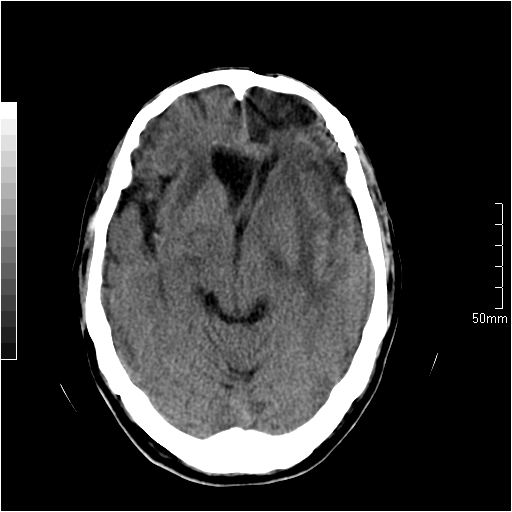

以下是引用天南地北在2007-6-25 12:39:00的发言:[br]有占位效应[br]支持术后复发

以下是引用zjzjr在2007-6-25 12:38:00的发言:[br]左侧复发,右侧转移。